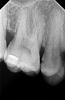

s390 Опубликовано 1 сентября, 2010 Поделиться Опубликовано 1 сентября, 2010 (изменено) Уважаемые стоматологи, проконсультируйте, пожалуйста по снимкам.Дело в том, что мне рекомендуют на левую верхнюю пятерку ставить коронку. Нельзя ли обойтись пломбой? Кроме того, на такой же верхней пятерке, но справа - как рекомендуете лечить кариес - идти к дырке по жевательной поверхности или есть вариант сбоку?Особенно интересует мнение Fury.Снимки выложил вот сюда одним архивом, так как в форум ну очень неудобно вставлять:http://ifolder.ru/19116505 Изменено 1 сентября, 2010 пользователем s390 Ссылка на комментарий

s390 Опубликовано 1 сентября, 2010 Автор Поделиться Опубликовано 1 сентября, 2010 Я понимаю, что врач будет делать так, как ему удобнее. Но хотелось бы услышать персональное мнение каждого врача или развернутый ответ.Ирина Анатольевна сказала, что будет снимать порядка 1/4 коронки. Ссылка на комментарий

Fil Опубликовано 4 сентября, 2010 Поделиться Опубликовано 4 сентября, 2010 Через жевательную поверхность, однозначно. если врач опытный, то лишних тканей зуба он не затронет. так что доверьтесь своему доктору. Ссылка на комментарий